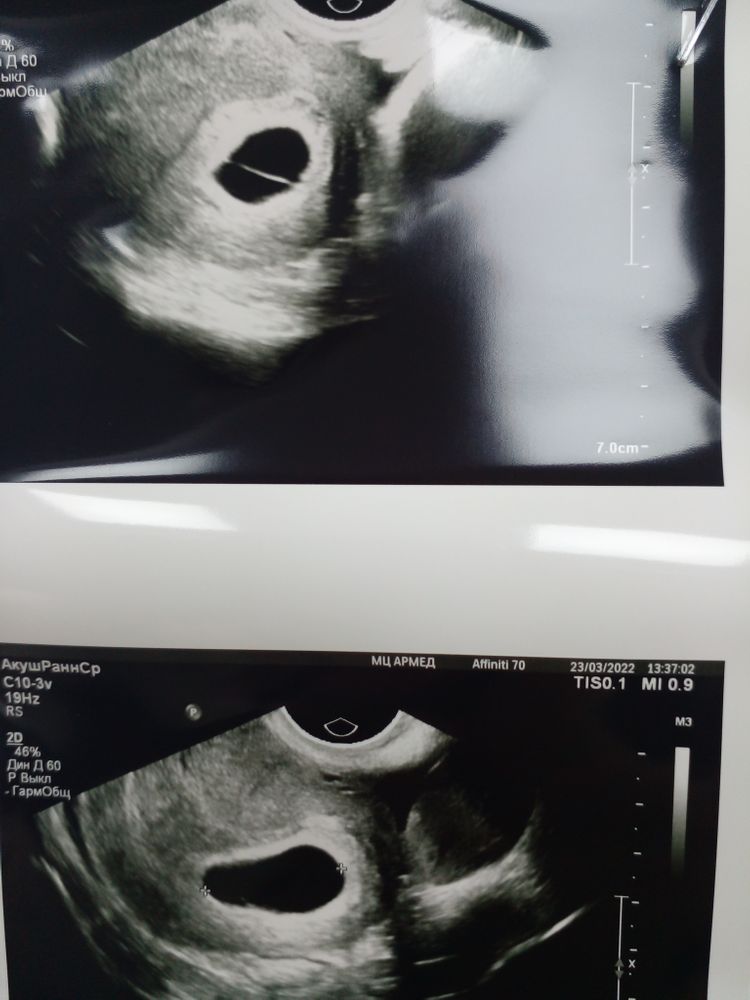

Изображение Эмбриона нет, звука сердца тоже! Посоветовали пересдать через 10 дней и следить за хгч! Мне не понятна нить вдоль плодного яйца? У кого так было ? Ольга Полянская,

На УЗИ 6 недель, пя и жм? Что видно? Сб?